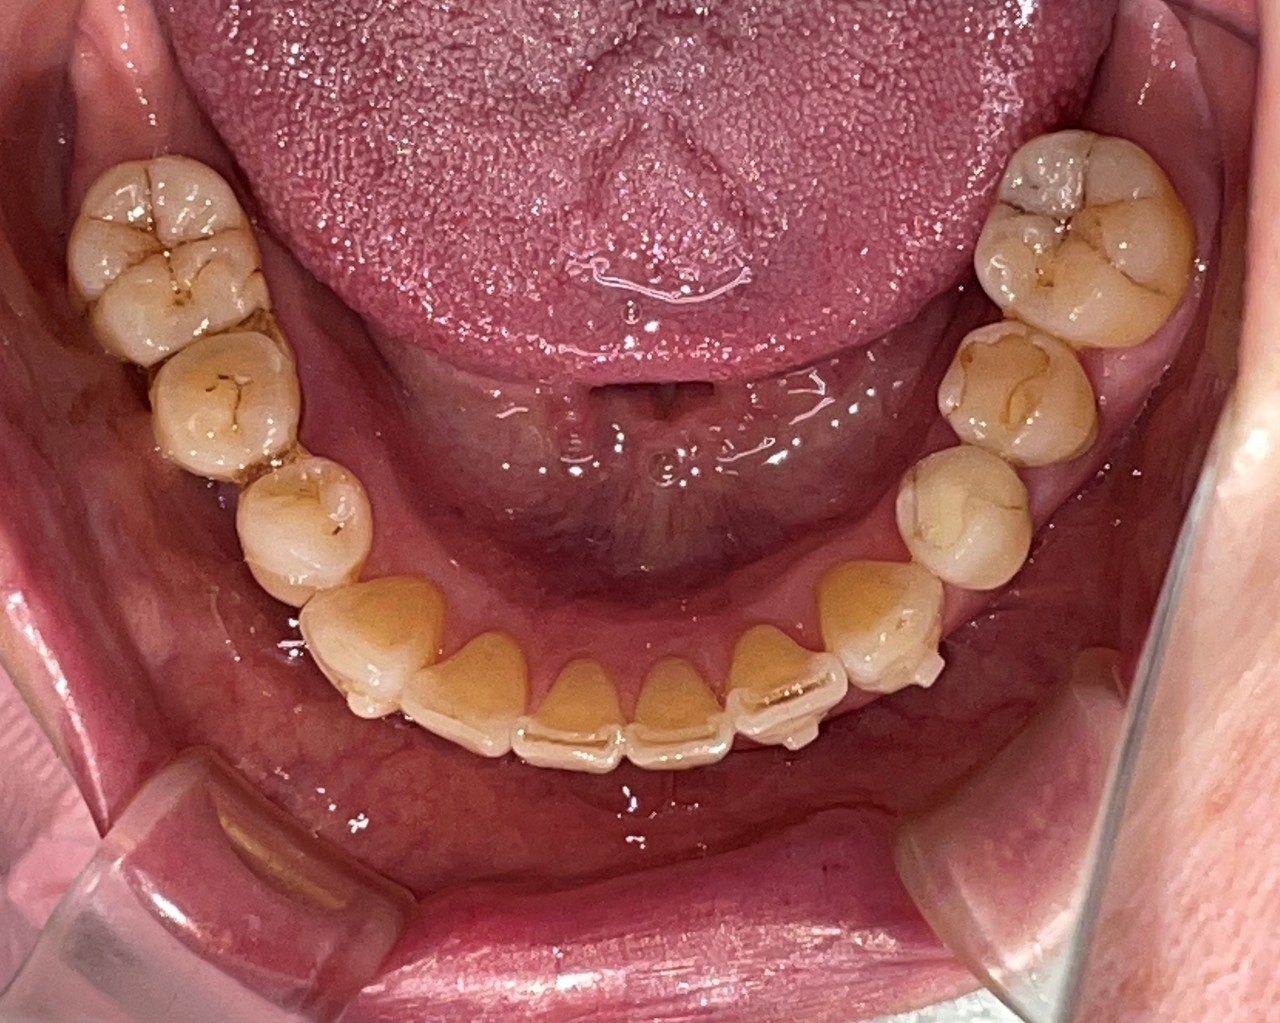

Before

After

矯正の種類 / invisalign GO

年齢・性別 / 30代女性

主訴  /  叢生、交叉咬合

治療期間 / 17ヶ月

費用 / 簡易検査 5,000円(税別) 精密検査 30,000円(税別)

両顎マウスピース 450,000円(税別) 両顎リテイナー料 60,000円(税別)

※マウスピース交換時別途調節料5,000円(税別)

副作用 / 口内炎・歯の移動に伴う痛み・知覚過敏 ※数日で収まる場合が多いです

リスク / 後戻り防止の為、夜のみマウスピースで保定を指示